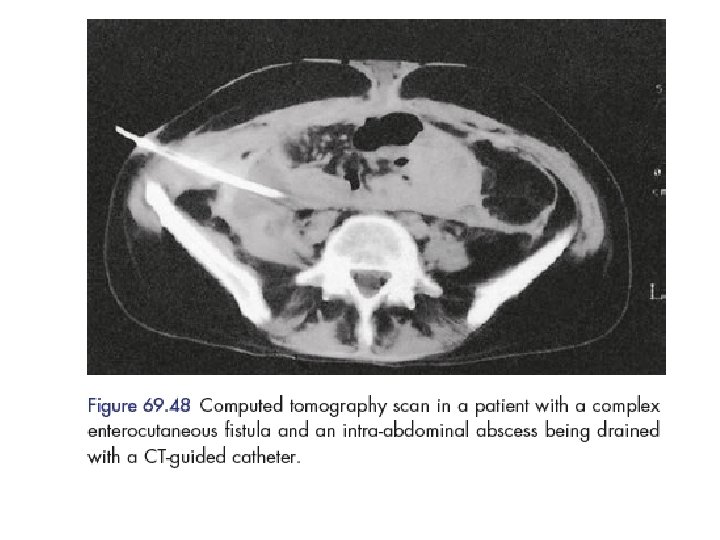

CT scan with oral contrast is considered the single best radiologic test locating the fistula defining its anatomy commenting on the gut surrounding fistula abdominal leaking presence of any intra-abdominal distal obstruction/pathology foreign bodies abscess CT scan is highly recommended for duodenal and pancreatic fistula. CT scan be therapeutic by helping in CTguided aspiration of intra-abdominal abscesses, if any.

Endoscopy may also be used occasionally though its principal use is in internal fistulas. Endoscopy is usually delayed till acute inflammation gets reduced. CT scan